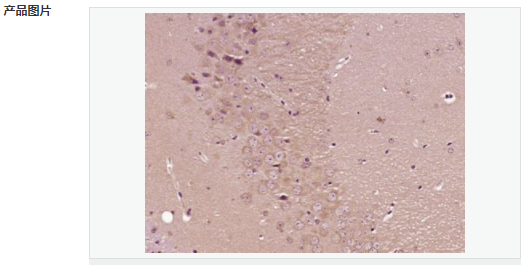

| 產品應用 | ELISA=1:5000-10000 IHC-P=1:100-500 IHC-F=1:100-500 IF=1:100-500 (石蠟切片需做抗原修復) not yet tested in other applications. optimal dilutions/concentrations should be determined by the end user. |

| 產品介紹 | This gene encodes a member of the fascin family of actin-binding proteins. Fascin proteins organize F-actin into parallel bundles, and are required for the formation of actin-based cellular protrusions. The encoded protein plays a critical role in cell migration, motility, adhesion and cellular interactions. Expression of this gene is known to be regulated by several microRNAs, and overexpression of this gene may play a role in the metastasis of multiple types of cancer by increasing cell motility. Expression of this gene is also a marker for Reed-Sternberg cells in Hodgkin's lymphoma. A pseudogene of this gene is located on the long arm of chromosome 15. [provided by RefSeq, Sep 2011] Function: Organizes filamentous actin into bundles with a minimum of 4.1:1 actin/fascin ratio. Plays a role in the organization of actin filament bundles and the formation of microspikes, membrane ruffles, and stress fibers. Important for the formation of a diverse set of cell protrusions, such as filopodia, and for cell motility and migration. Subunit: Associates with beta-catenin. Interacts with PLXNB3. Subcellular Location: Cytoplasm, cytoskeleton. Cell projection, filopodium. Cell projection, invadopodium. Cytoplasm, cytosol. Note=In glioma cells, partially colocalizes with F-actin stress fibers in the cytosol. Tissue Specificity: Ubiquitous. Post-translational modifications: Phosphorylation on Ser-39 inhibits the actin-binding ability of fascin. Similarity: Belongs to the fascin family. SWISS: Q16658 Gene ID: 6624 Database links: Entrez Gene: 6624 Human Entrez Gene: 14086 Mouse Omim: 602689 Human SwissProt: Q16658 Human SwissProt: Q61553 Mouse Unigene: 118400 Human Unigene: 289707 Mouse Unigene: 199526 Rat Important Note: This product as supplied is intended for research use only, not for use in human, therapeutic or diagnostic applications. FSCN1為細胞骨架肌動蛋白的一種,該蛋白有蛋白結合,橋連、肌動蛋白絲結合的功能。 主要參與細胞增殖、肌動蛋白細胞骨架組織和生物發生、肌動蛋白絲束形成。Fascin也是一種actin結合蛋白,它的功能是把F-actin聚集捆綁成束,與細胞的運動相關。病理情況下,各種惡性腫瘤細胞經常高表達Fascin。 |